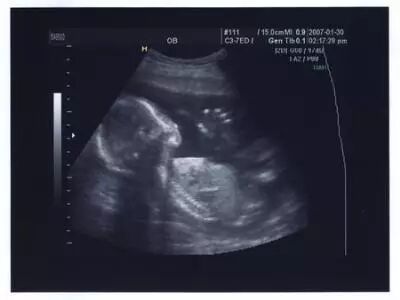

超声波图像曾抓拍到男婴的勃起图片,不过由于生殖器官差异的原因,只有男性能在X光片上看出来。